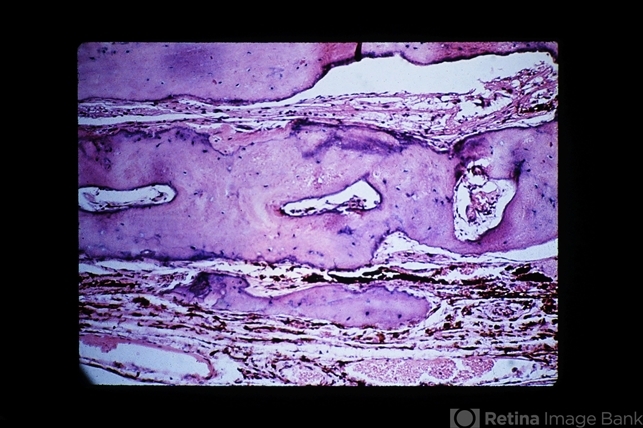

- bone, choroid

- Mature bone on the surface of the choroid.